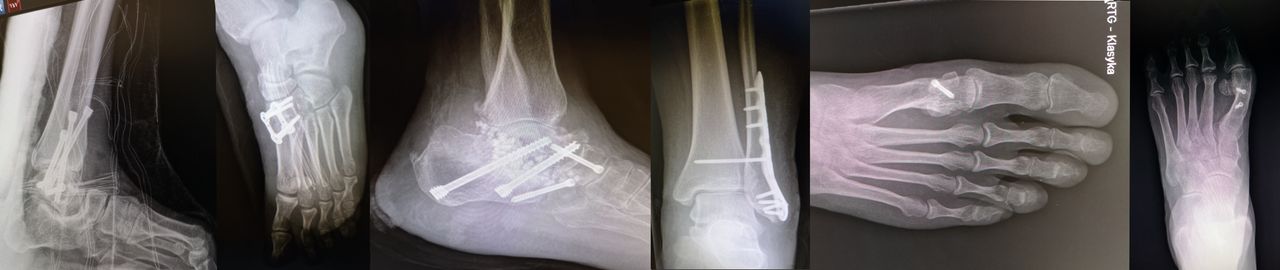

ZAPRASZAM DO REJESTRACJI PRZEZ APLIKACJĘ MyDr. Na co dzień pracuję w Klinice Ortopedii Uniwersyteckiego Centrum Klinicznego w Gdańsku. Zajmuję się diagnostyką i leczeniem chirurgicznym urazów oraz schorzeń przewlekłych układu mięśniowo-szkieletowego ze szczególnym uwzględnieniem stopy i stawu skokowego. Oprócz tego wykonuję także: USG narządu ruchu kolana, barku, nadgarstka, biodra i stawu skokowego. Iniekcje leków przeciwbólowych i przeciwzapalnych, kwasów hialuronowych, osocza bogatopłytkowego - także pod kontrolą USG Zabiegi artroskopowe w schorzeniach stawu kolanowego, skokowego i barkowego. Leczenie operacyjne deformacji stóp i stawu skokowego, zespołów uciskowych nerwów obwodowych jak i wielu innych przypadłości związanych z narządem ruchu. Wierzę, że każda wizyta powinna być kompleksowym podejściem do problemów pacjenta. Podczas każdej porady stawiam sobie za zadanie rozwiązanie problemu bólu u pacjenta, nakreślenie planu dalszej diagnostyki oraz przedstawienie najbardziej odpowiednich metod leczniczych z uwzględnieniem zarówno metod zabiegowych jak i niezabiegowych.

4 tyg.temu miałam wstawiony drut K.w palec u stopy, od dwóch dni odczuwam ból oraz zauważyłam, ze palec przekręcił się o 90 stopni.Powodem zastosowania druta, było zestarzałe zwichnięcie palca.

Ponieważ pojedynczy drut nie chroni palca przed rotacją mogło dojść do jego obrócenia się przy niefortunnym ruchu. Powinna Pani czym prędzej zobaczyć się z ortopedą żeby ocenił sytuację i nastawił palca prawidłowo. Nie powinno wiązać się to z dużym dyskomfortem, ostatecznie można to wykonać w znieczuleniu miejscowym, ale im szybciej tym lepiej!